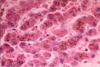

What are the key features of this tissue that was biopsied from the liver following a bile duct obstruction?

What has likely happened secondary to a bile duct obstruction in this patient?

• what would you expect to see histologically?

Ascending Cholangitis has been superimposed on a bile duct obstruction as a result of bacterial infiltration

**Key Histological features below:

• Neutrophils in the bile duct lining and also in the lumen